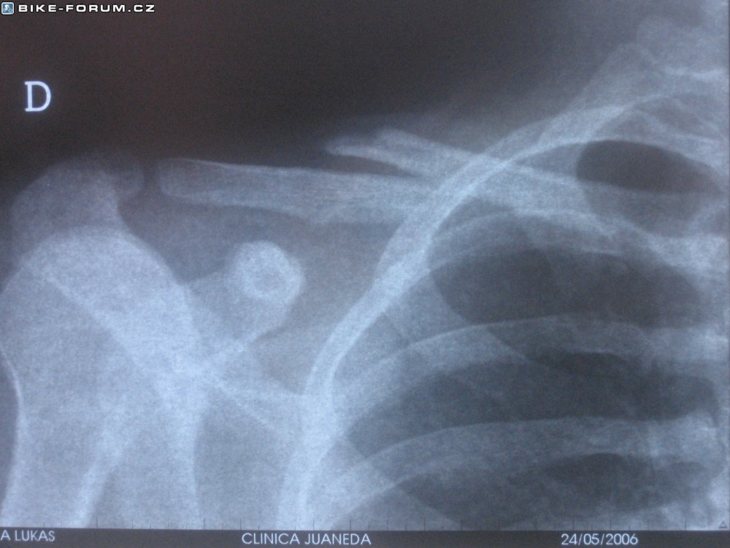

Klíční kost

to je na dvou mistech krach? au au